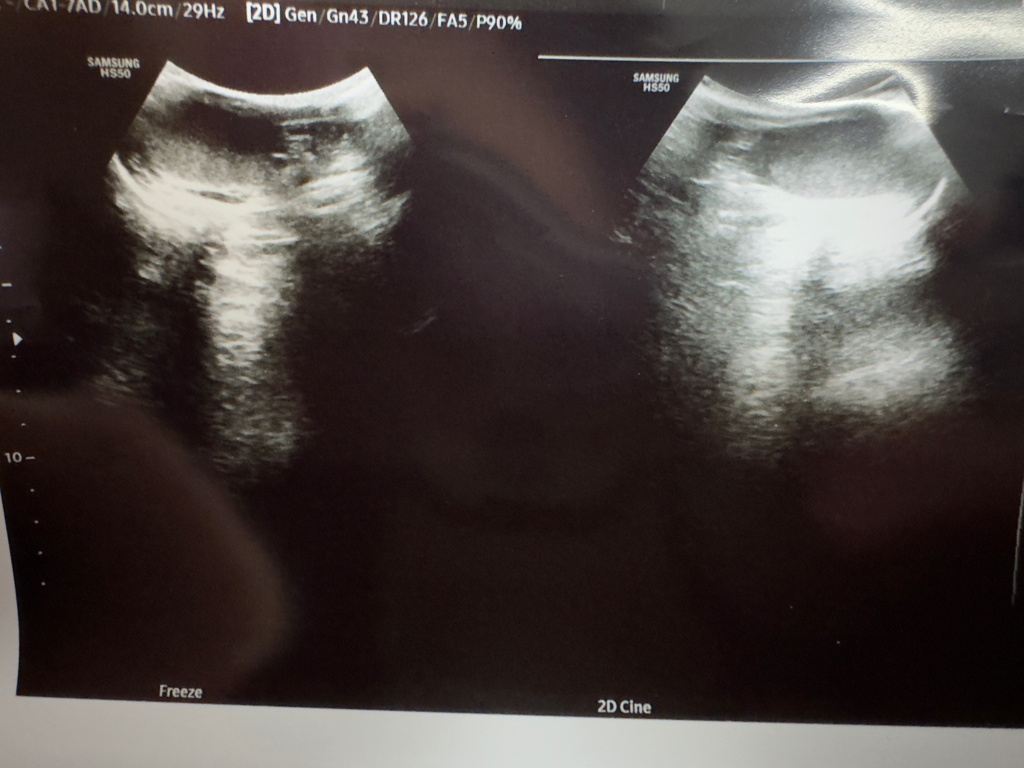

우선 올려주신 초음파 사진은 복부장기를 주로 보는데 쓰이는 convex probe로 시행한 초음파 검사인 것 같네요. (그렇다고 convex probe를 고환을 보는데 쓰면 안되는 건 아닙니다)

사진이 작지만 좌측은 부고환/우측이 고환으로 생각되는데, 올려주신 사진상으로는 고환암으로 생각되는 병변은 없습니다.

하지만 depth 조절도 제대로 안하고 찍은 사진으로 평가에 제한이 있겠습니다.